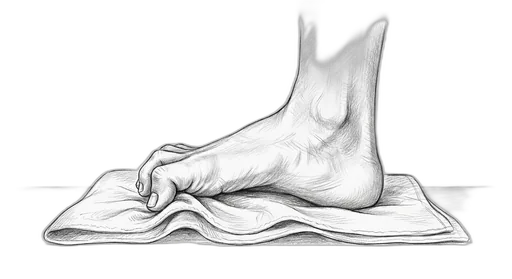

Towel Curl

This exercise strengthens the small muscles on the bottom of your foot — called the intrinsic foot muscles. These are the muscles that support your arch from the inside, kind of like a built-in orthotic. When they're strong, they help distribute your body weight more evenly, protect against overpronation (your foot rolling inward too much), and take stress off the plantar fascia, tendons, and joints.

What to expect: You may not feel dramatic changes in the first few weeks, but stick with it — these small muscles take time to build. By several weeks, many patients notice better arch support, less foot fatigue at the end of the day, and improved balance. The research shows measurable strength gains within a few weeks.

How to do it: Sit in a chair with your bare feet flat on the floor. Lay a small towel flat under your foot. Curl your toes to scrunch the towel toward you — like you're trying to pick it up with your toes — then spread your toes flat and repeat. Try to use all five toes, not just the big one.

| Mild | 3–5 sec per curl | 10 | 3 | 1×/day | Focus on curling with all your toes evenly — it takes practice, and that's okay |

| Moderate | 3 sec per curl | 8 | 2 | 1×/day | Use a thin towel on a smooth floor to make it easier |

| Severe | 2 sec per curl | 5 | 1 | 1×/day | If the towel is too hard, just practice curling your toes on carpet without it |

How to progress: Start with a thin towel on a smooth floor → thicker towel → place a small water bottle at the far end of the towel for added resistance. When seated feels easy, try it standing.

⚠ When to skip this: Hold off if you're recovering from hammertoe surgery or an acute plantar plate tear (first 4 weeks). Your surgeon will let you know when it's safe to start.